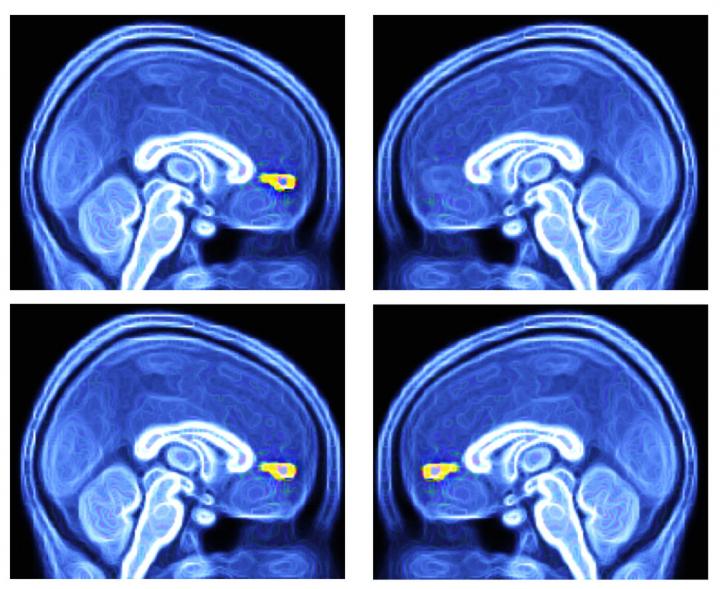

Using functional magnetic resonance imaging (fMRI), the team was able to measure the response of autistic children to different environmental cues by imaging a specific part of the brain involved in assigning value to social interactions.

In the study, the team led by Kishida and P. Read Montague, Ph.D., of Virginia Tech, tested the responsiveness of the brain's ventral medial prefrontal cortex (vmPFC) to visual cues that represented highly-valued social interaction in children diagnosed with ASD compared to typically developing (TD) children. The study included 40 participants ranging in age from 6 to18; 12 had ASD and 28 were TD.

According to the study, the average response of the vmPFC was significantly lower in the ASD group than in the TD group. Using images as a single stimulus to capture 30 seconds of fMRI data was sufficient to differentiate the ASD and TD groups, Kishida said.

"How the brain responded to these pictures is consistent with our hypothesis that the brains of children with autism do not encode the value of social exchange in the same way as typically developing children," he said.